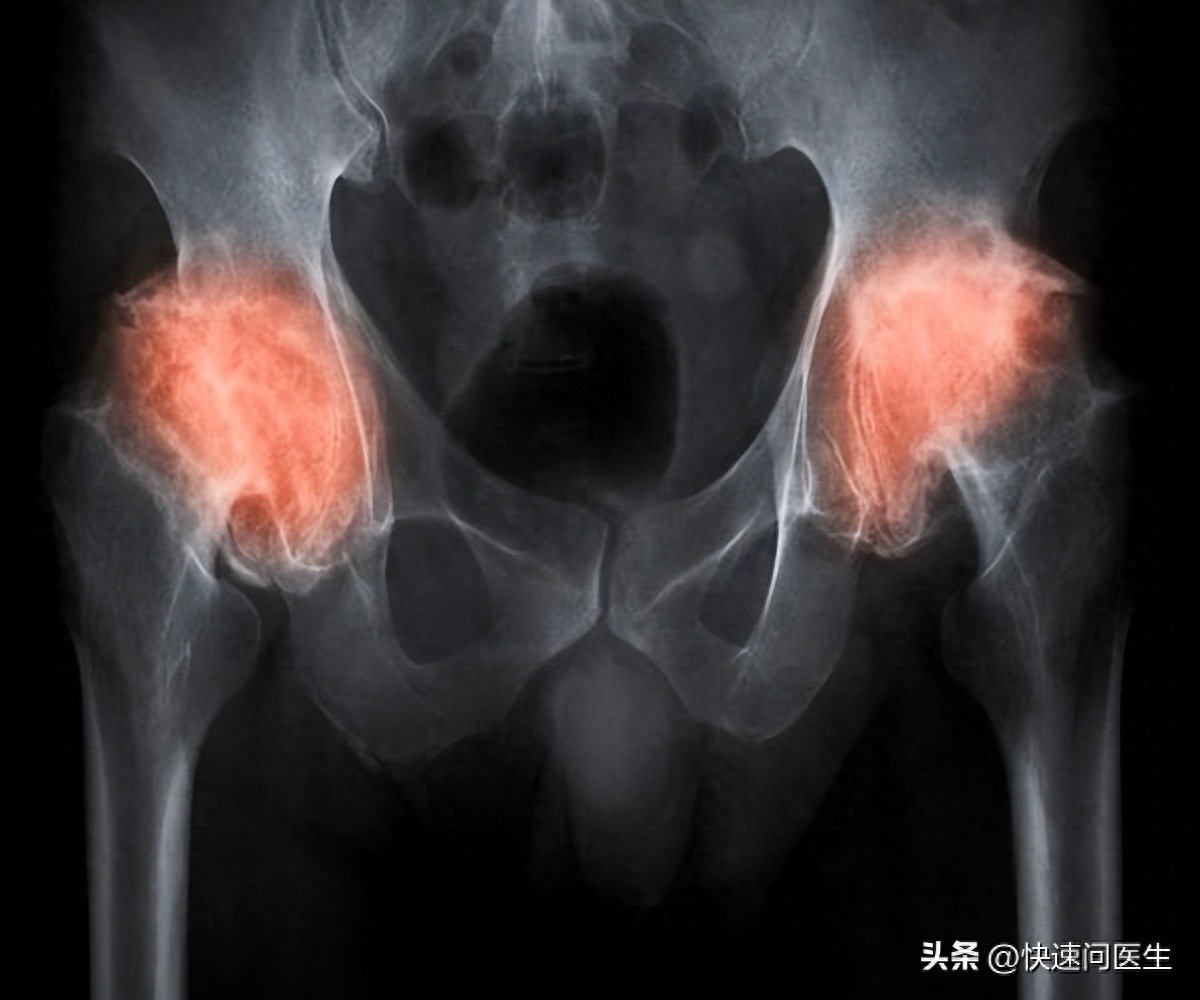

髋关节在人们的日常生活中扮演着关键角色,一旦遭遇严重磨损,行走能力将受到损害。尤其是对于中老年朋友来说,若髋关节因长期磨损或伴随其他疾病而受损开yun体育app官方下载入口,极有可能导致残疾。鉴于此,掌握髋关节的保养方法显得尤为关键。现在,我将向大家介绍如何正确保养髋关节,敬请关注。 1、注意行走姿势 髋关节在人体行走过程中扮演着至关重...